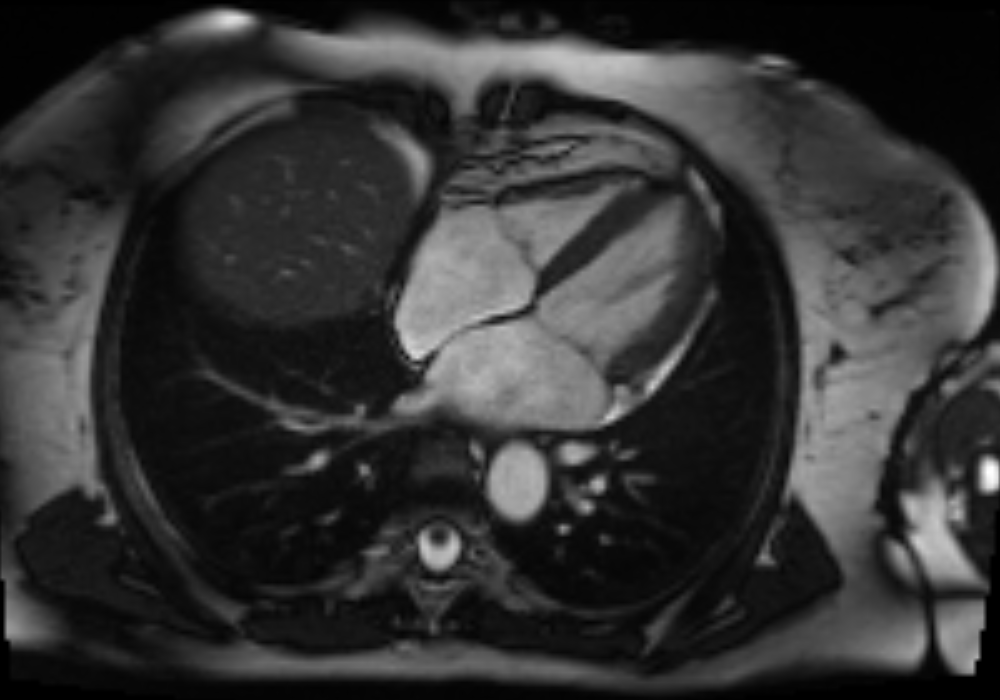

Figure 1: Three cardiovascular magnetic resonance (CMR) images showing the long-axis four-chamber view of the heart. Left: a heart with normal mitral valve. Middle: a heart with normal mitral valve when the valve leaflets are open. Right: a heart with mitral regurgitation. The red dotted line denotes the mitral valve.